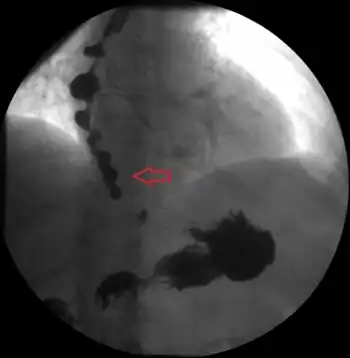

Diagnosis

The diagnosis is generally confirmed by esophageal manometry.[2] DES is present when more than a fifth of swallows results in distal esophageal contractions.[2] NE is present if the average strength of the contractions of the distal esophagus is greater than 180 mmHg but the contraction of the esophagus is otherwise normal.[2]